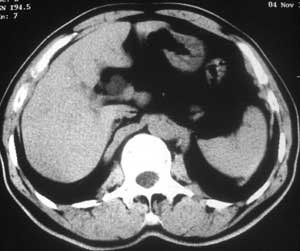

患者,男,57岁,梗阻性黄疸10余天。

这个病例胰头无明显增大,胆总管扩张明显而肝内胆管扩张更不明显,病程较短,

注意到十二指肠乳头明显突出,但尚光滑。分析以下可能性:

1、十二指肠乳头本身的病变,如乳头炎症;

2、急性乳头水肿,胆总管下端结石排石后乳头水肿;

3、壶腹部胆总管下端肿瘤累及十二指肠乳头。

十二指肠乳头粘膜慢性非特异性炎症